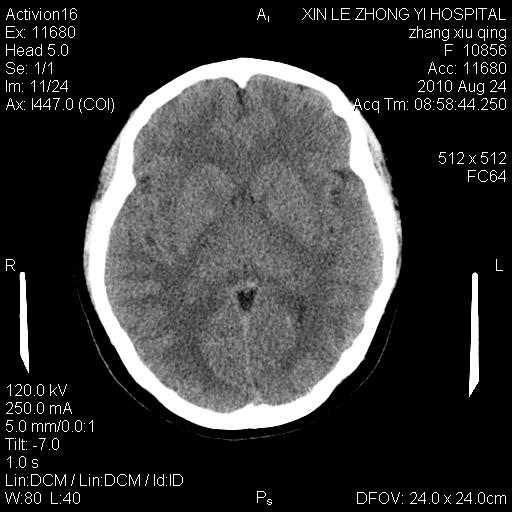

标题: CT28569:看看鞍上池正常吗 [打印本页]

标题: CT28569:看看鞍上池正常吗

女 24 偶有头晕

未见明显异常,必要时可作mri

未见明显异常,必要时可作mri 。

伪影干扰下,所见无水肿、无占位,建议定期复查。